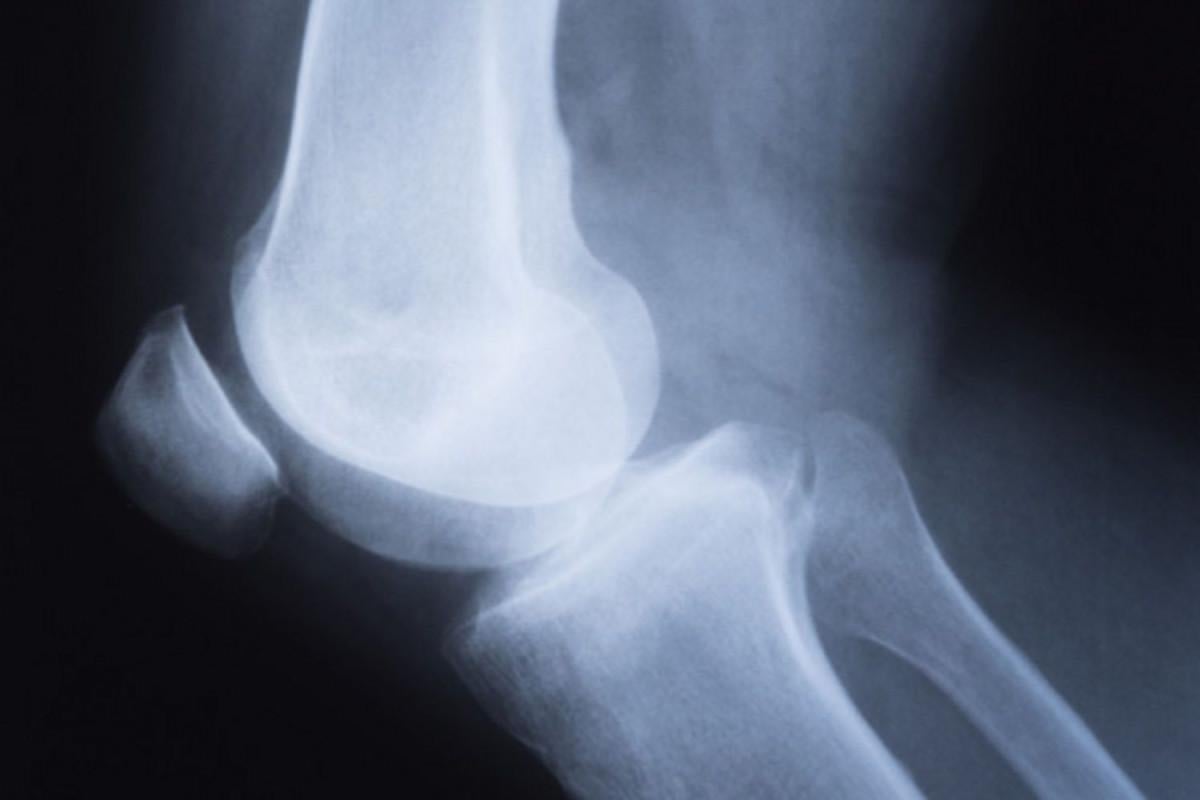

Dizinizden gelen çıtırtı sesi krepitus olarak adlandırılır. Dizinizde başka bir belirtiniz yoksa, krepitus için özel bir tedaviye gerek yoktur. Krepitus, eklem hareketi sırasında kıkırdağın eklem yüzeyine veya diz çevresindeki diğer yumuşak dokulara sürtünmesi sonucu oluşur.

Kıkırdak Aşınması: Diz kapağının altındaki kıkırdak yüzeyler zamanla aşınabilir veya hasar görebilir. Bu durumda, diz eğilip doğrulurken kıkırdaklar arasında sürtünme artabilir ve bu da çıtırtı veya çatırtı seslerine neden olabilir.

Tendonlar ve Bağlar: Diz kapağının etrafında bulunan tendonlar ve bağlar, hareket sırasında sürtünmeye ve gerilime maruz kalabilir. Bu da seslerin oluşmasına katkıda bulunabilir.

Sinovyal Sıvı Hacmi: Diz eklemi içinde bulunan sinovyal sıvı, eklemin düzgün çalışmasını sağlar ve sürtünmeyi azaltır. Ancak, bu sıvı miktarı azalırsa veya konsistansı değişirse, dizde sesler oluşabilir.